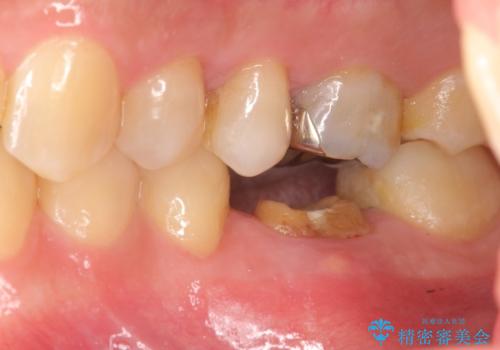

放置してしまった歯 根管治療からの機能回復

- 放置してしまった歯が痛み、いよいよ耐えられなくなり来院されました。

根管治療の途中で放置してしまっていた歯を、最終的に機能回復できるよう治療を行っていきます。

治療途中の歯の放置は、より虫歯を進行させてしまい抜歯に至ってしまうこともあるので注意が必要です。